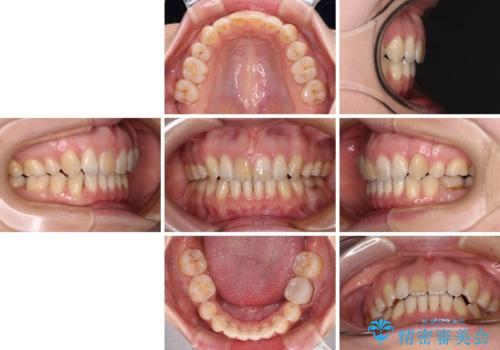

- 上の前歯の飛び出した感じを改善したいとのことで来院された患者様です。

上顎左右第一小臼歯2本、下顎左右第二小臼歯2本を抜歯し、ワイヤー装置にて口元を引っ込めるよう矯正治療を行うこととしました。

上下の前歯に隙間が空くほど上顎前歯が前に飛び出していましたが、抜歯矯正により上下前歯がぴったりと付くほど口元を引っ込めることができました。